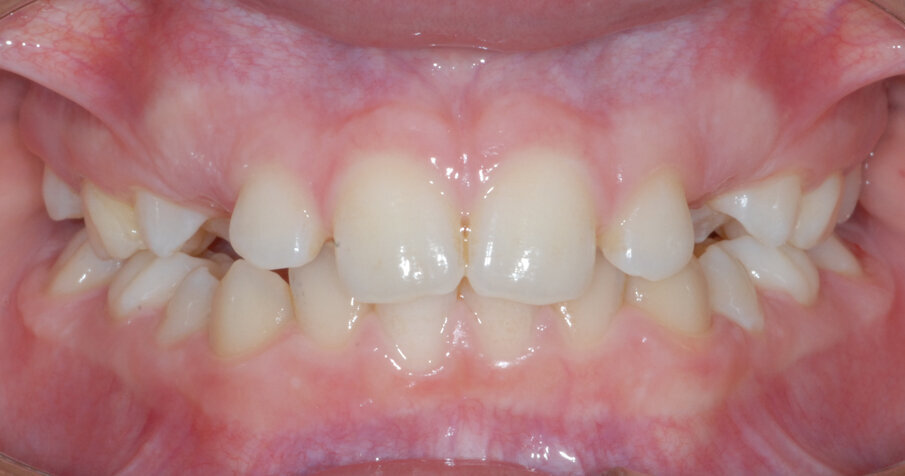

Riccardo 6 anni, viene sottoposto in prima visita ad ortopantomografia (Figg. 12, 13) delle arcate dentarie che evidenzia un deficit di spazio per l’eruzione dei canini permanenti. Si acquisiscono i modelli virtuali tramite scanner intraorale, viene fatta la prova bande e viene realizzato un espansore del palato modello Leaf expander® (Leone, Sesto Fiorentino (FI), Italia). L’espansore viene cementato su “E” (Fig. 14).

Fig. 13_Vista frontale iniziale.